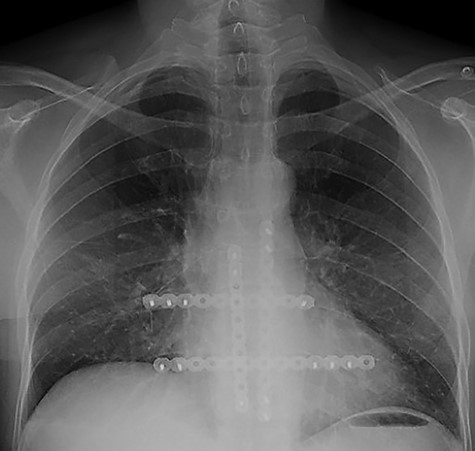

The first case at our institution was a 39-year-old woman who had a history of left breast carcinoma treated with left mastectomy, axillary node clearance and immediate reconstruction under the care of the breast team 3 years prior to presentation. She had no significant co-morbidities. Her past surgical history consisted of the aforementioned oncological operation, appendicectomy and cholecystectomy. She had completed adjuvant oncological therapy in the form of chemoradiotherapy and maintenance hormonal therapy. Her post-operative histology was consistent with a fully excised left breast ductal carcinoma and spread to three out of nine lymph nodes. Due to positive oestrogen receptor-2 status, she had been placed on hormonal therapy. She re-presented with chest wall and sternal pain and subsequent computer tomography (CT) imaging demonstrated a suspicious looking lytic lesion in the mid-sternum (Fig. 1). She underwent a biopsy of this lesion, which confirmed the diagnosis. She had been taking opioid medication for the pain. She was seen in clinic and counselled for partial sternectomy and reconstruction. She underwent partial sternectomy and underwent reconstruction with vertical and horizontal Synthes® plates. Her post-operative recovery was unremarkable. Post-operative histology was consistent with metastatic breast carcinoma completely excised. The recovery was uncomplicated and the patient was seen in clinic with a satisfactory chest radiograph demonstrating the sternal Synthes® plates (Fig. 2).